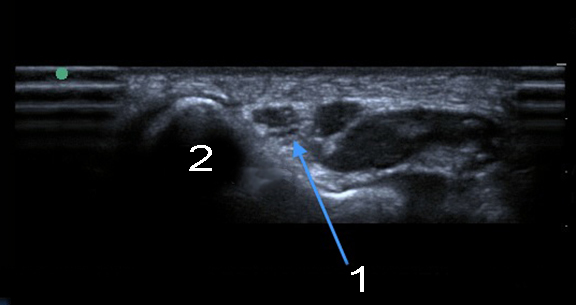

1. Image : Coude : Vue transverse du nerf ulnaire au niveau du tunnel cubital

2. Épicondyle médial